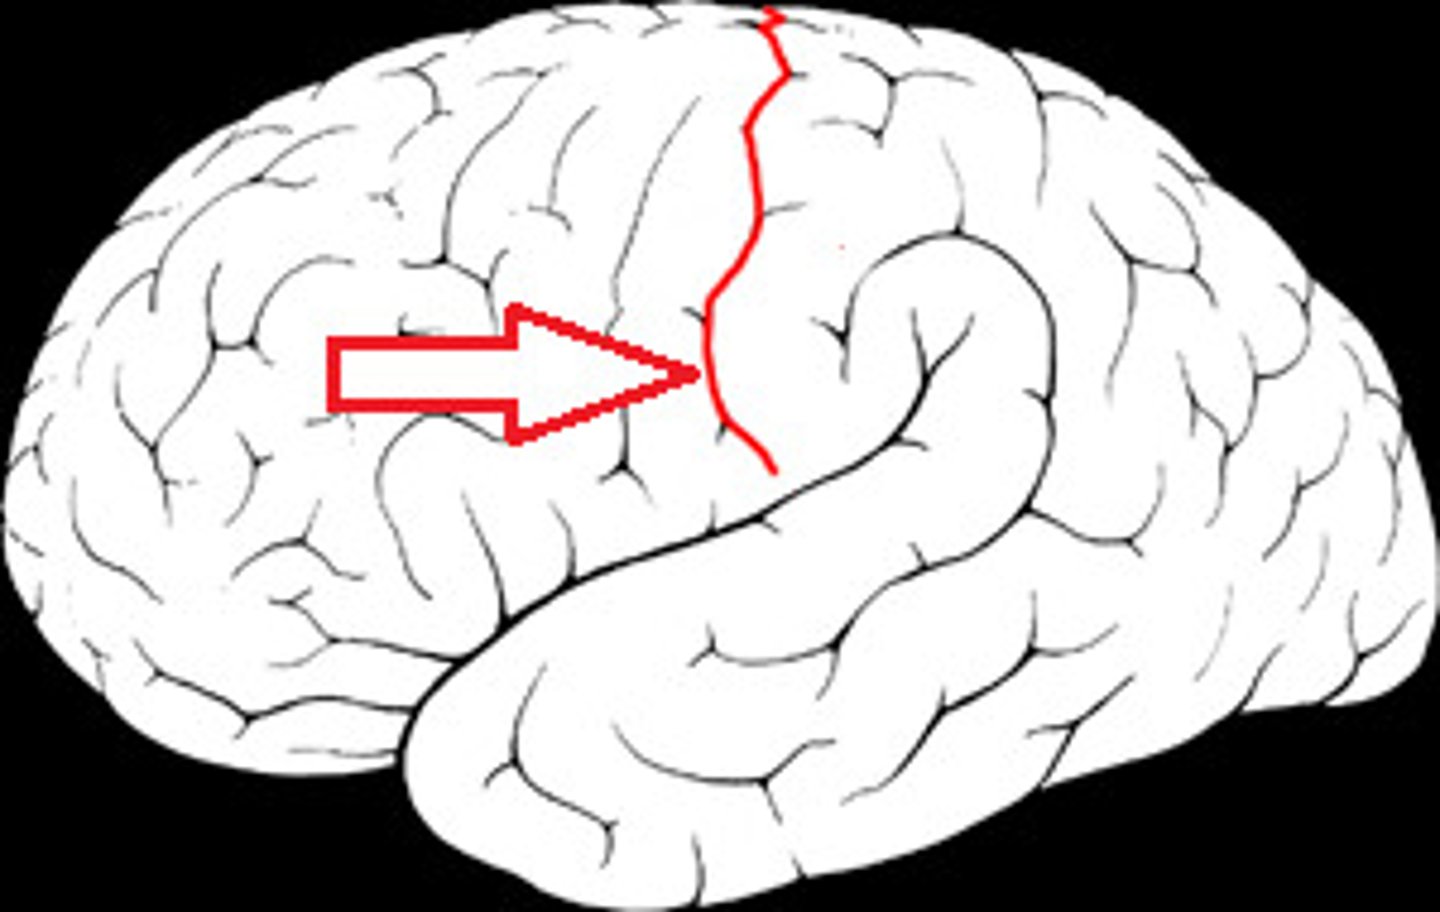

Central Sulcus

Precentral Gyrus

Postcentral Gyrus